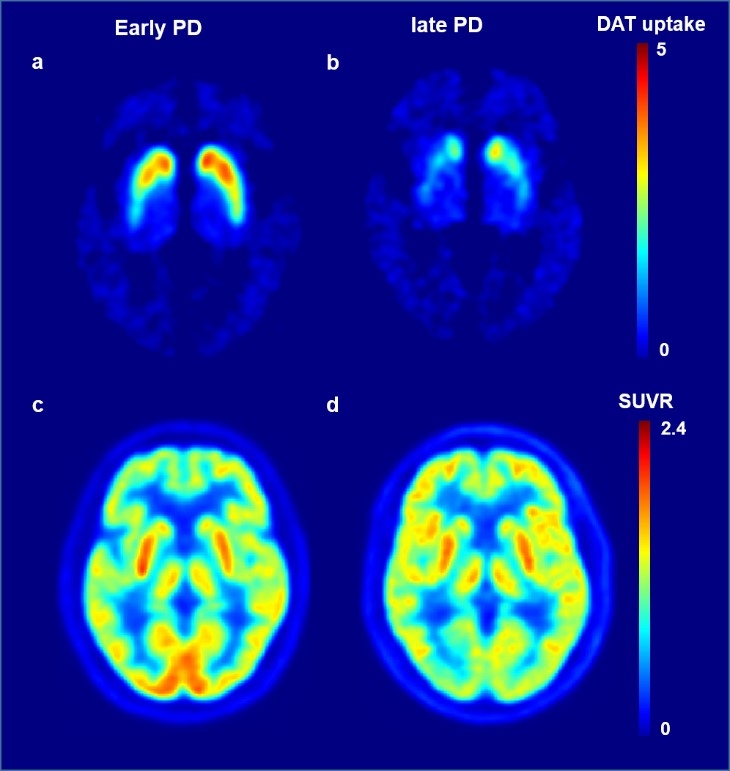

Purpose: While many studies have explored the link between biomarkers and cognitive decline in Parkinson's disease (PD), a more comprehensive approach is needed, combining striatal dopamine depletion, cerebral glucose metabolism, and cognitive assessments. In this study, we investigated the relationships between striatal dopamine transporter (DAT) uptake, cerebral glucose hypometabolism, and cognition, as well as the potential progression pattern of these changes in PD.Methods: We enrolled 62 patients with PD and 33 healthy controls. The subjects underwent N-(3-[18F]fluoropropyl)-2β-carbomethoxy-3β-(4-iodophenyl)nortropane (FP-CIT) PET/CT, [18F] fluorodeoxyglucose (FDG) PET/CT, and detailed neuropsychological testing. The mean standard uptake value ratio (SUVR) value of the regions showing significantly lower metabolism in PD patients was defined as SUVR[hypo]. The relationship between striatal DAT uptake and SUVR[hypo] was assessed using general linear models, while their impact on cognitive function was evaluated with multivariate linear regression. Additionally, the pattern of their changes was assessed using an event-based model.

Results: Compared to the control group, PD patients exhibited glucose hypometabolism in specific cortical regions. DAT uptake in the anterior and posterior putamen was positively correlated with SUVR[hypo]. Decreased DAT uptake in the anterior putamen and caudate nucleus was associated with lower z-score in visuospatial function. Decreased DAT uptake in the posterior and anterior putamen occurred first, followed by PD-related cerebral hypometabolism, and visuospatial function.

Conclusion: This study highlights the interconnectedness of dopaminergic depletion, cerebral glucose hypometabolism, and visuospatial dysfunction, proposing that striatal DAT uptake may serve as an early biomarker for cerebral hypometabolism and cognitive impairment in PD.